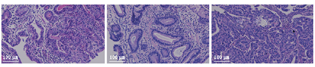

入院后完善相关检查,血常规、肝肾功能、电解质、凝血功能、传染病四项(乙型肝炎、丙型肝炎、梅毒、HIV)、类风湿因子、结缔组织全套、磷脂相关抗体、病毒全套、1,3-β-D葡聚糖试验、半乳糖甘露醇聚糖抗原检测、C反应蛋白(CRP)、降钙素原、叶酸、甲状腺功能、甲状腺相关抗体、B型钠尿肽、尿便常规、神经节苷脂抗体谱(抗GM1、GM2、GM3、GD1a、GD1b、GD2、GD3、GQ1b抗体IgG)未见明显异常。心电图:正常范围心电图。脑脊液压力:140 mmH2O(1 mmH2O=0.009 8 kPa)。脑脊液化验:白细胞46×106/L,淋巴细胞75%,浆细胞7%,嗜中性粒细胞5%;蛋白定性:阳性,定量:793.2 mg/L;糖及氯化物正常,抗酸染色及墨汁染色、腺苷脱氨酶阴性。血及脑脊液:自身免疫性脑炎抗体阴性。脑脊液脱落细胞学:镜下见少量淋巴细胞。头颅MRI平扫+增强示:鞍区占位性病变,考虑垂体瘤;双侧基底节区腔隙性脑梗死或扩大的血管间腔(图1)。肿瘤标志物:癌胚抗原63.22 ng/ml;非小细胞肺癌抗原21-1 3.65 ng/ml;肿瘤相关抗原72-4 11.82 U/ml。副肿瘤标志物:抗-Yo抗体阳性。

胸部、全腹CT平扫+增强示:(1)胃小弯侧占位,考虑癌并周围淋巴结肿大。(2)右肺下叶小肺大泡,左肺上叶舌段轻微炎症。(3)肝左叶小囊肿。(4)左侧肾上腺稍增粗。(5)前列腺钙化灶。胃镜及病理活组织检查(活检)诊断:(1)慢性食管炎;(2)贲门胃底、胃角溃疡伴高级别腺上皮内瘤变(图2,图3)。